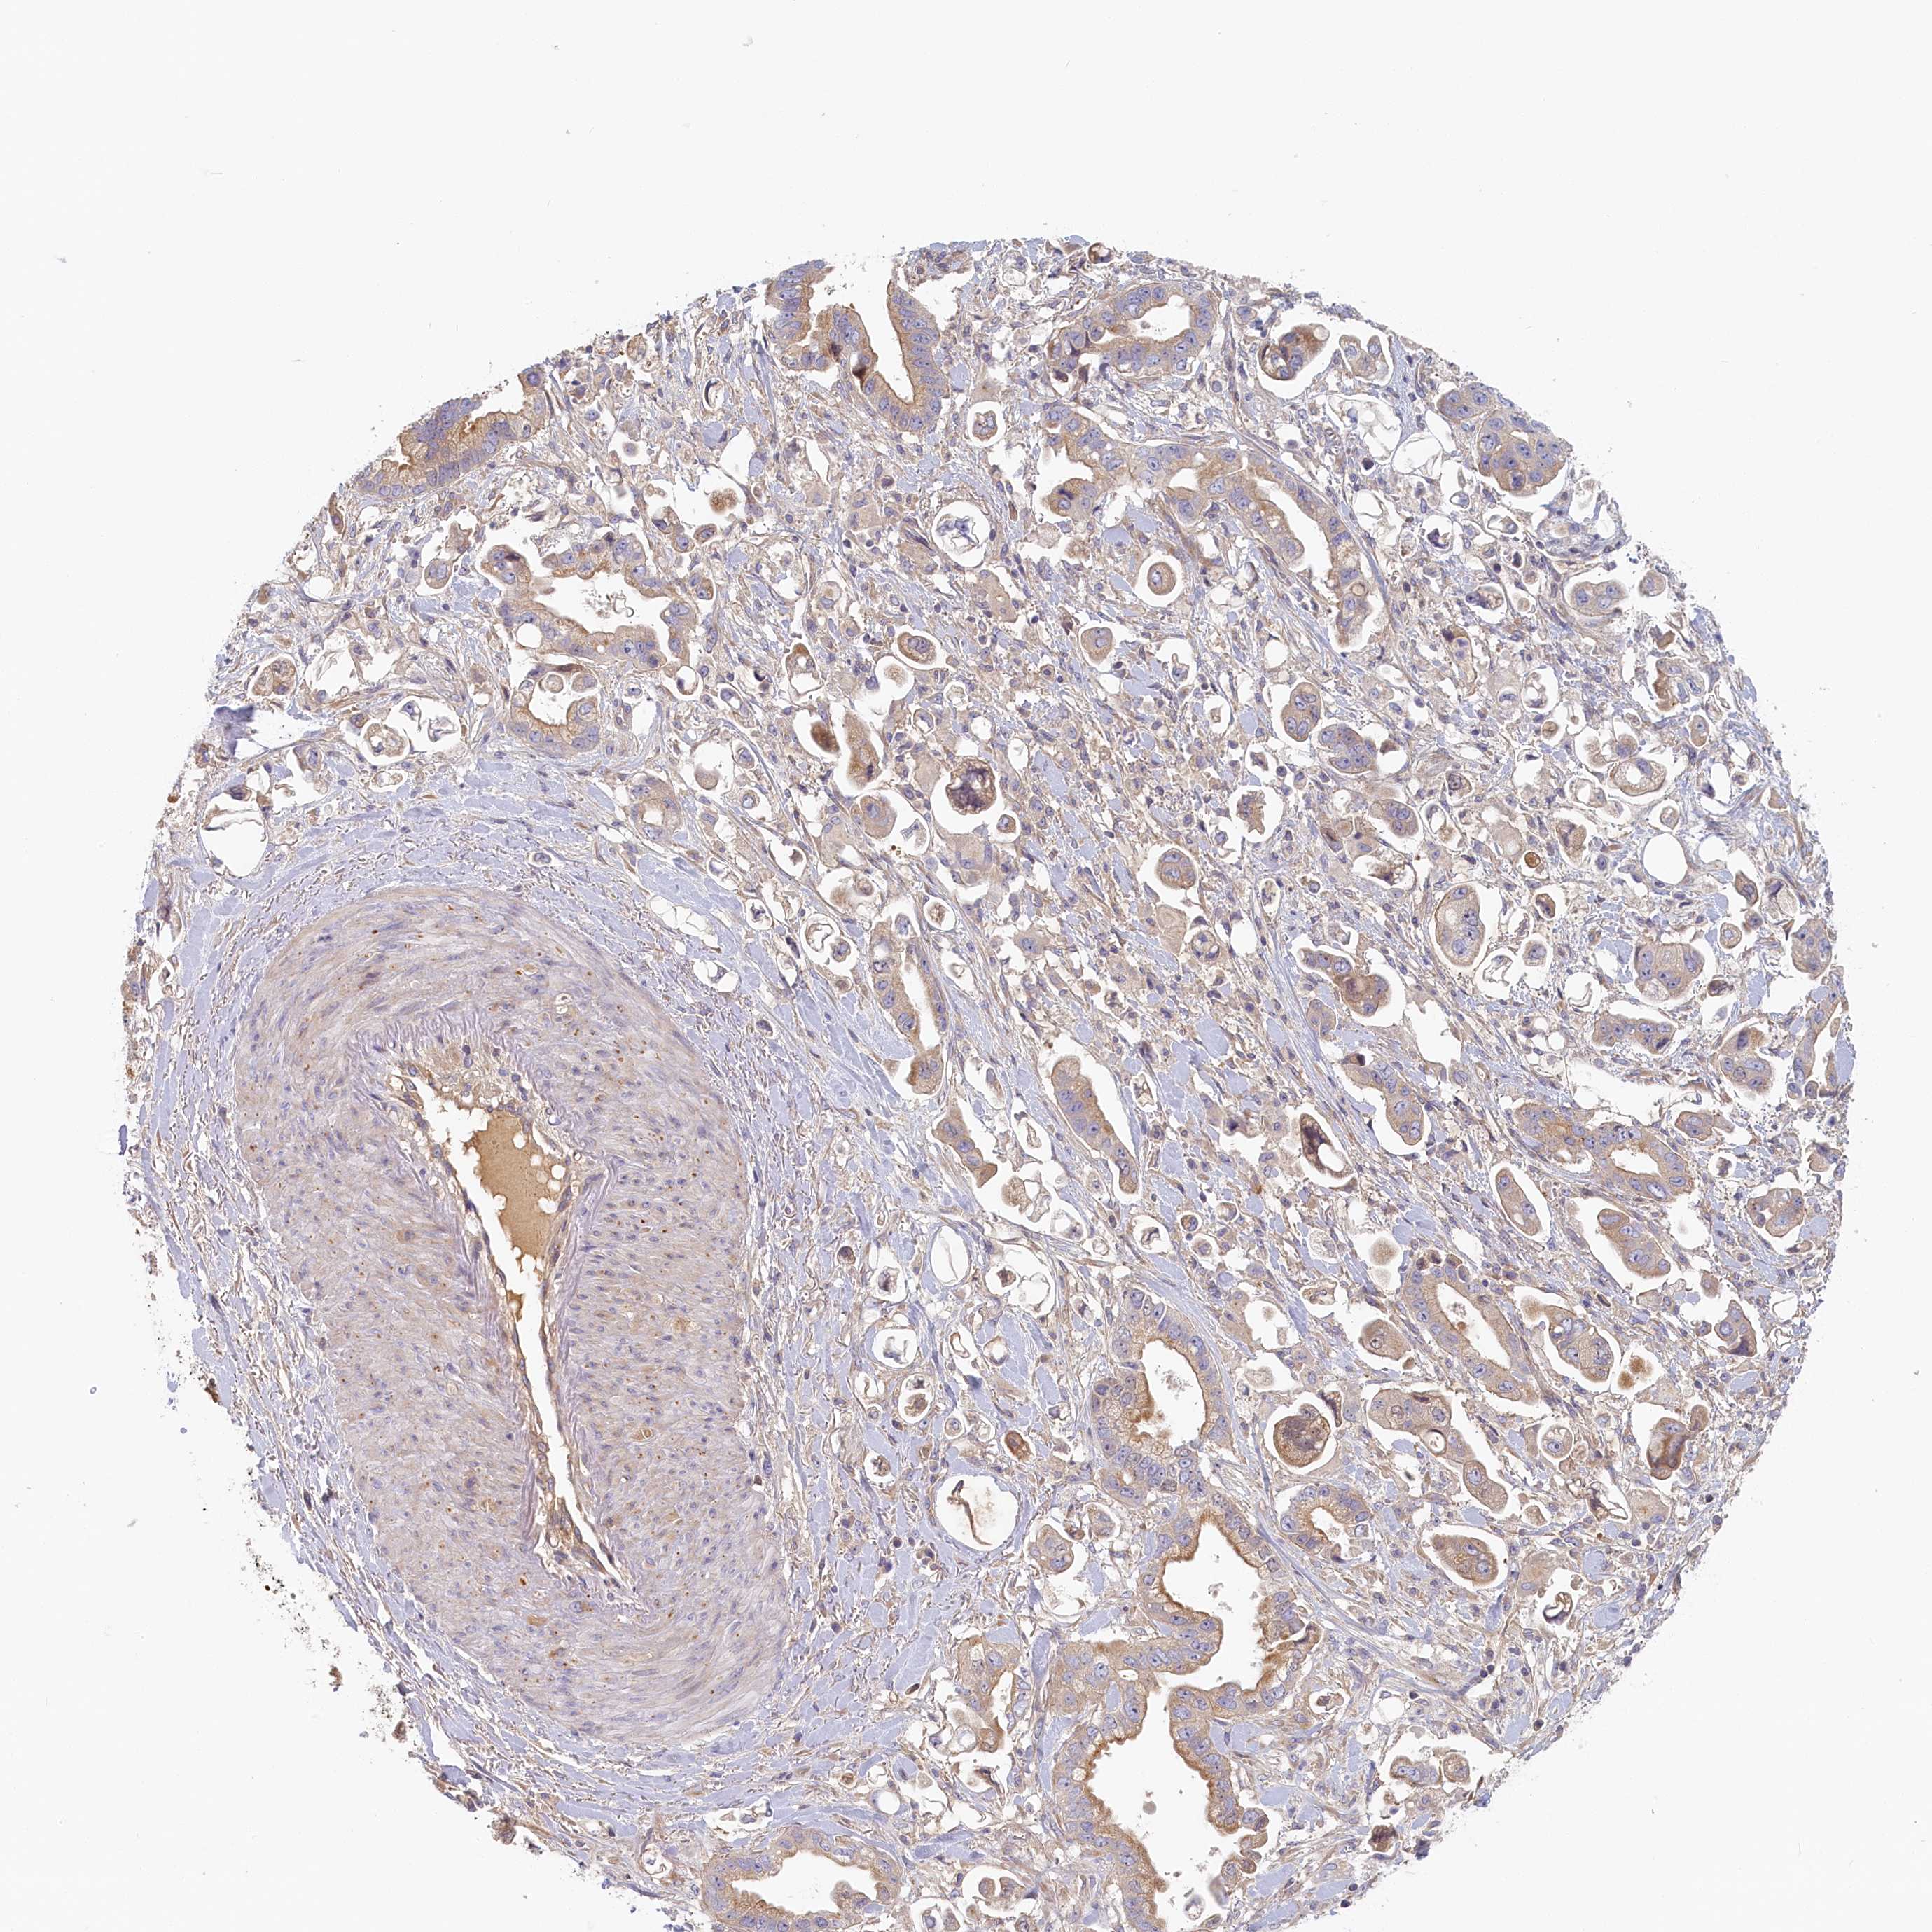

STOMACH CANCER - Protein expressioni

A mouse-over function shows sample information and annotation data. Click on an image to view it in a full screen mode. Samples can be filtered based on level of antibody staining by selecting one or several of the following categories: high, medium, low and not detected. The assay and annotation is described here.

Note that samples used for immunohistochemistry by the Human Protein Atlas do not correspond to samples in the TCGA dataset.

Antibody stainingi

Antibody staining in the annotated cell types in the current human tissue is reported as not detected, low, medium, or high, based on conventional immunohistochemistry profiling in selected tissues. This score is based on the combination of the staining intensity and fraction of stained cells.

Each image is clickable and will lead to virtual microscopy that enables deeper exploration of all samples and also displays staining intensity scores, fraction scores and subcellular localization as well as patient and tissue information for each sample.

Antibody HPA041019

Antibody HPA042033

Staining

High

Medium

Low

Not detected

Intensity

Strong

Moderate

Weak

Negative

Quantity

>75%

75%-25%

<25%

None

Location

Nuclear

Cytoplasmic/membranous

Cytoplasmic/membranous,nuclear

Adenocarcinoma, NOS